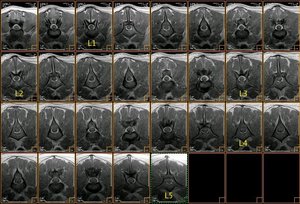

Resonancia magnética lumbo-sacra de pastor alemán |

La médula espinal acaba en L5, donde empieza la cola de caballo |